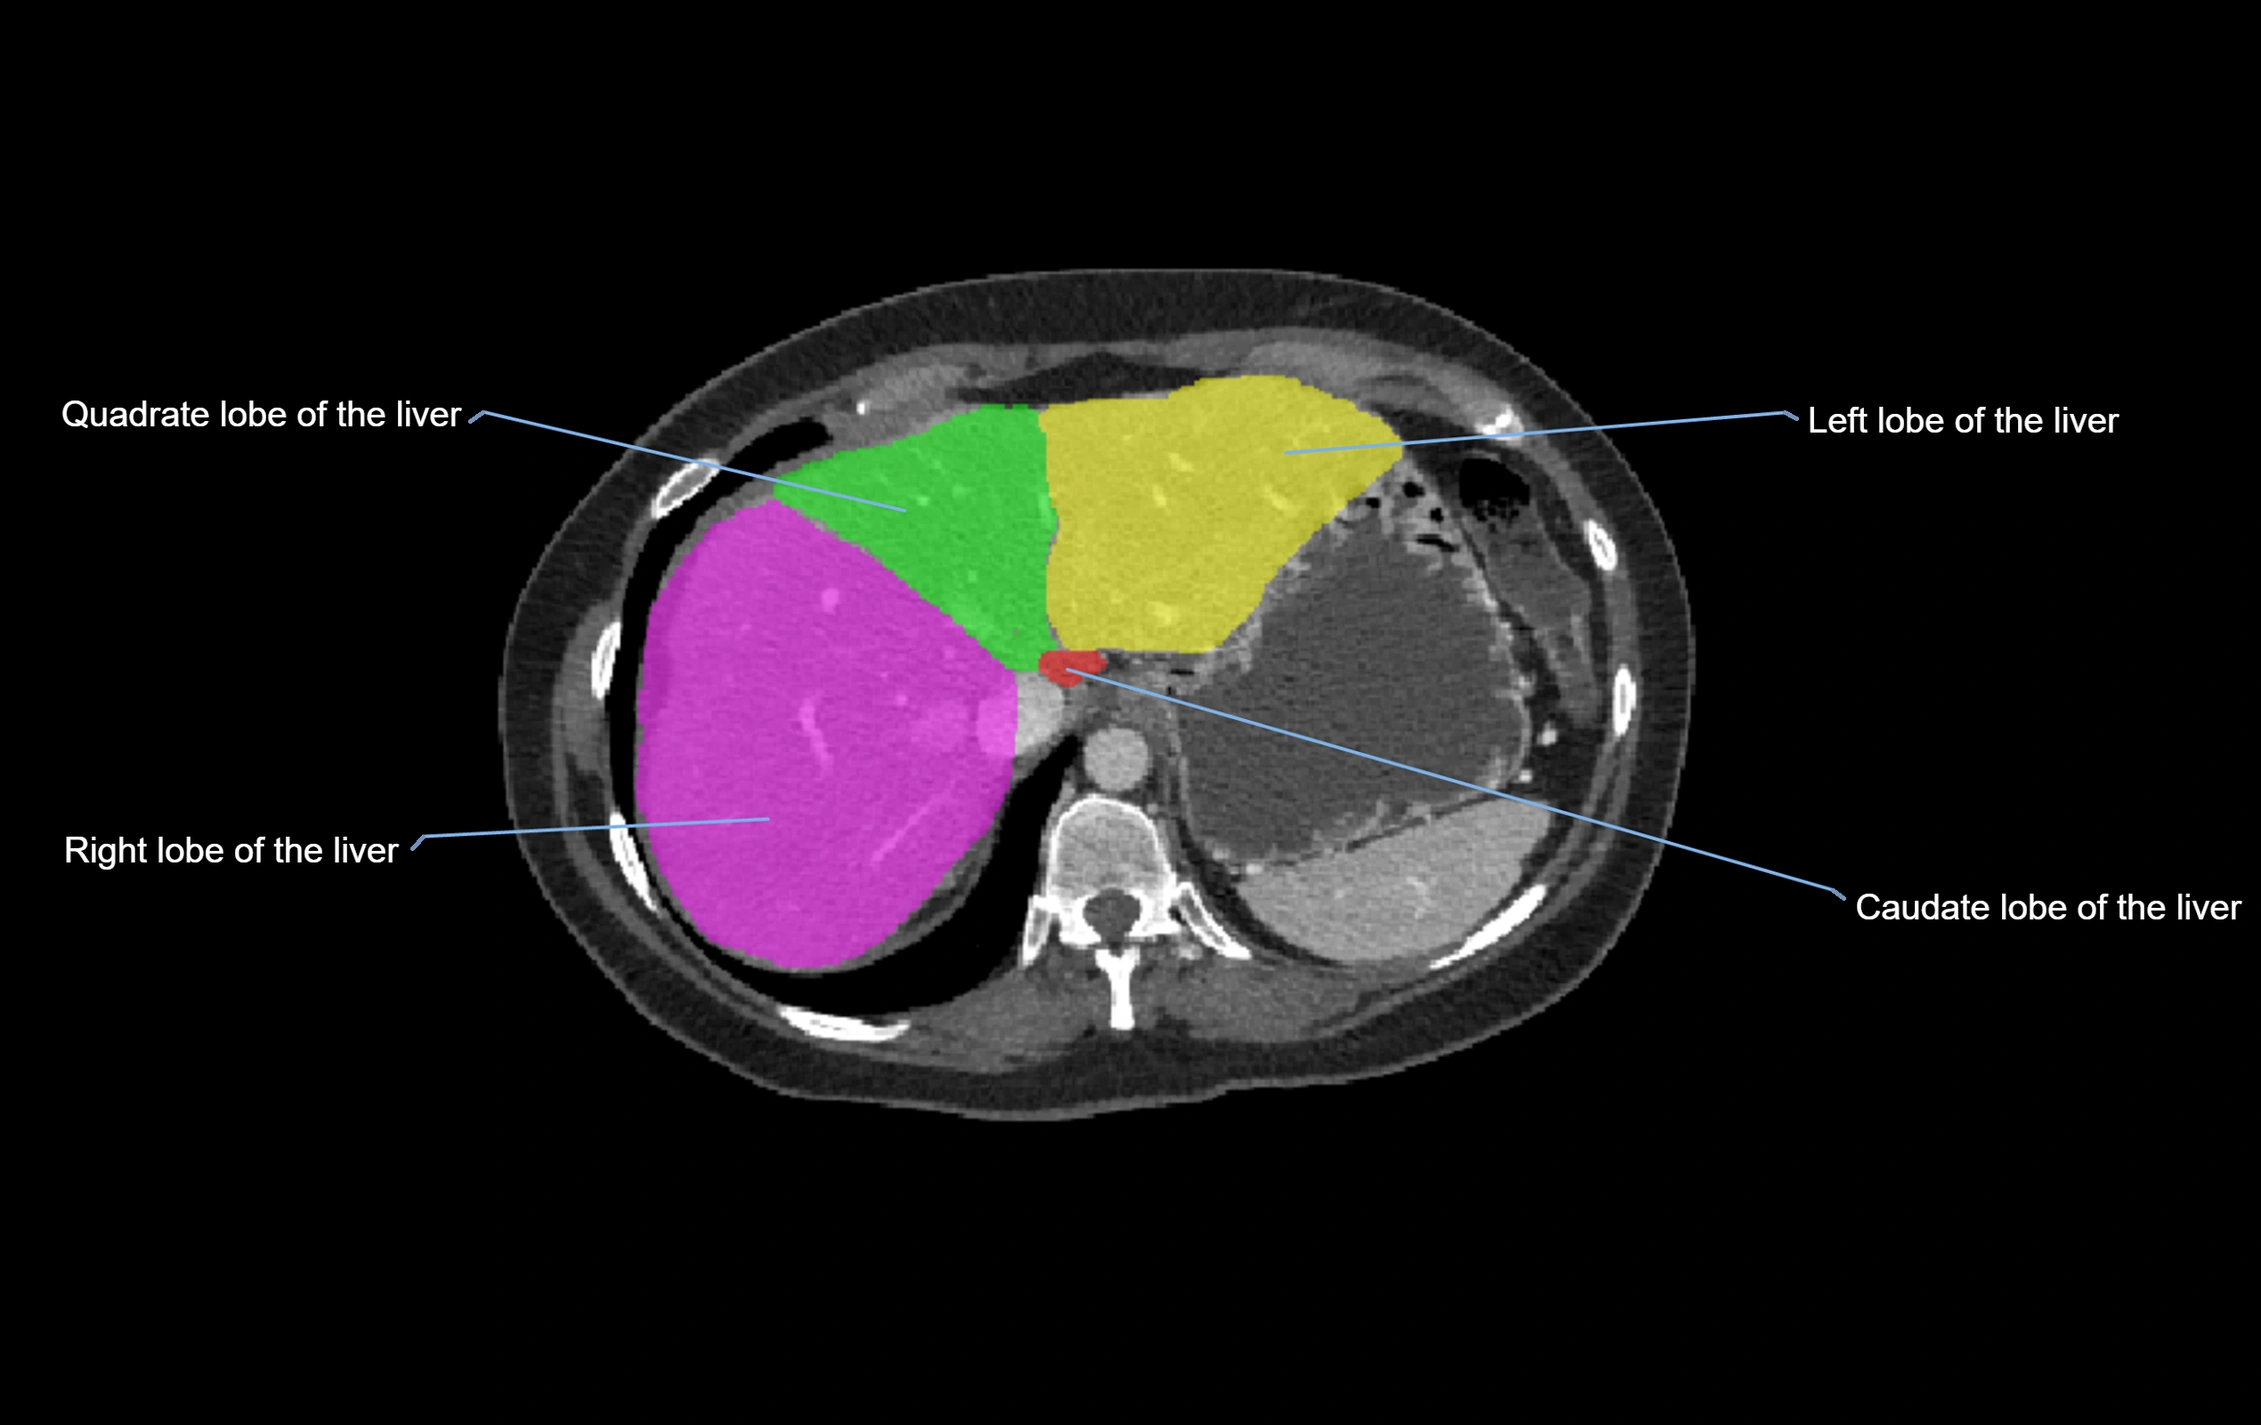

CT Image

image